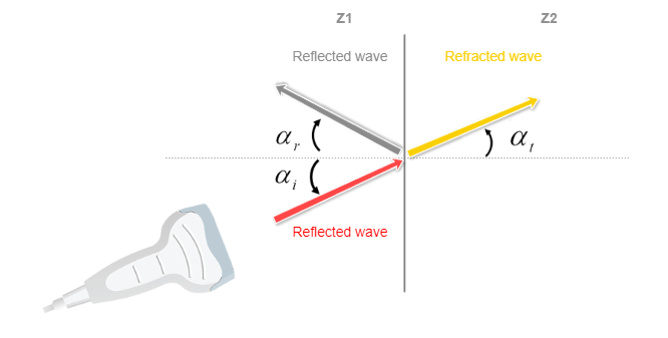

Reflection / Refraction

Another phenomenon is the Refraction of a sound wave, which occurs when the wave travels between tissues with different propagation speeds. The refraction is defined by the change in the direction of the sound wave and is determined by Snell’s law. We can see how the direction of the wave has changed or deviated, as it passes through the interface.

Transmitted sound waves will continue its propagation, and will certainly be again reflected, refracted, or transmitted. The “rules” of reflection are identical to those that apply to light. An incident wave that collides with an inclined smooth surface will not be reflected to the source.